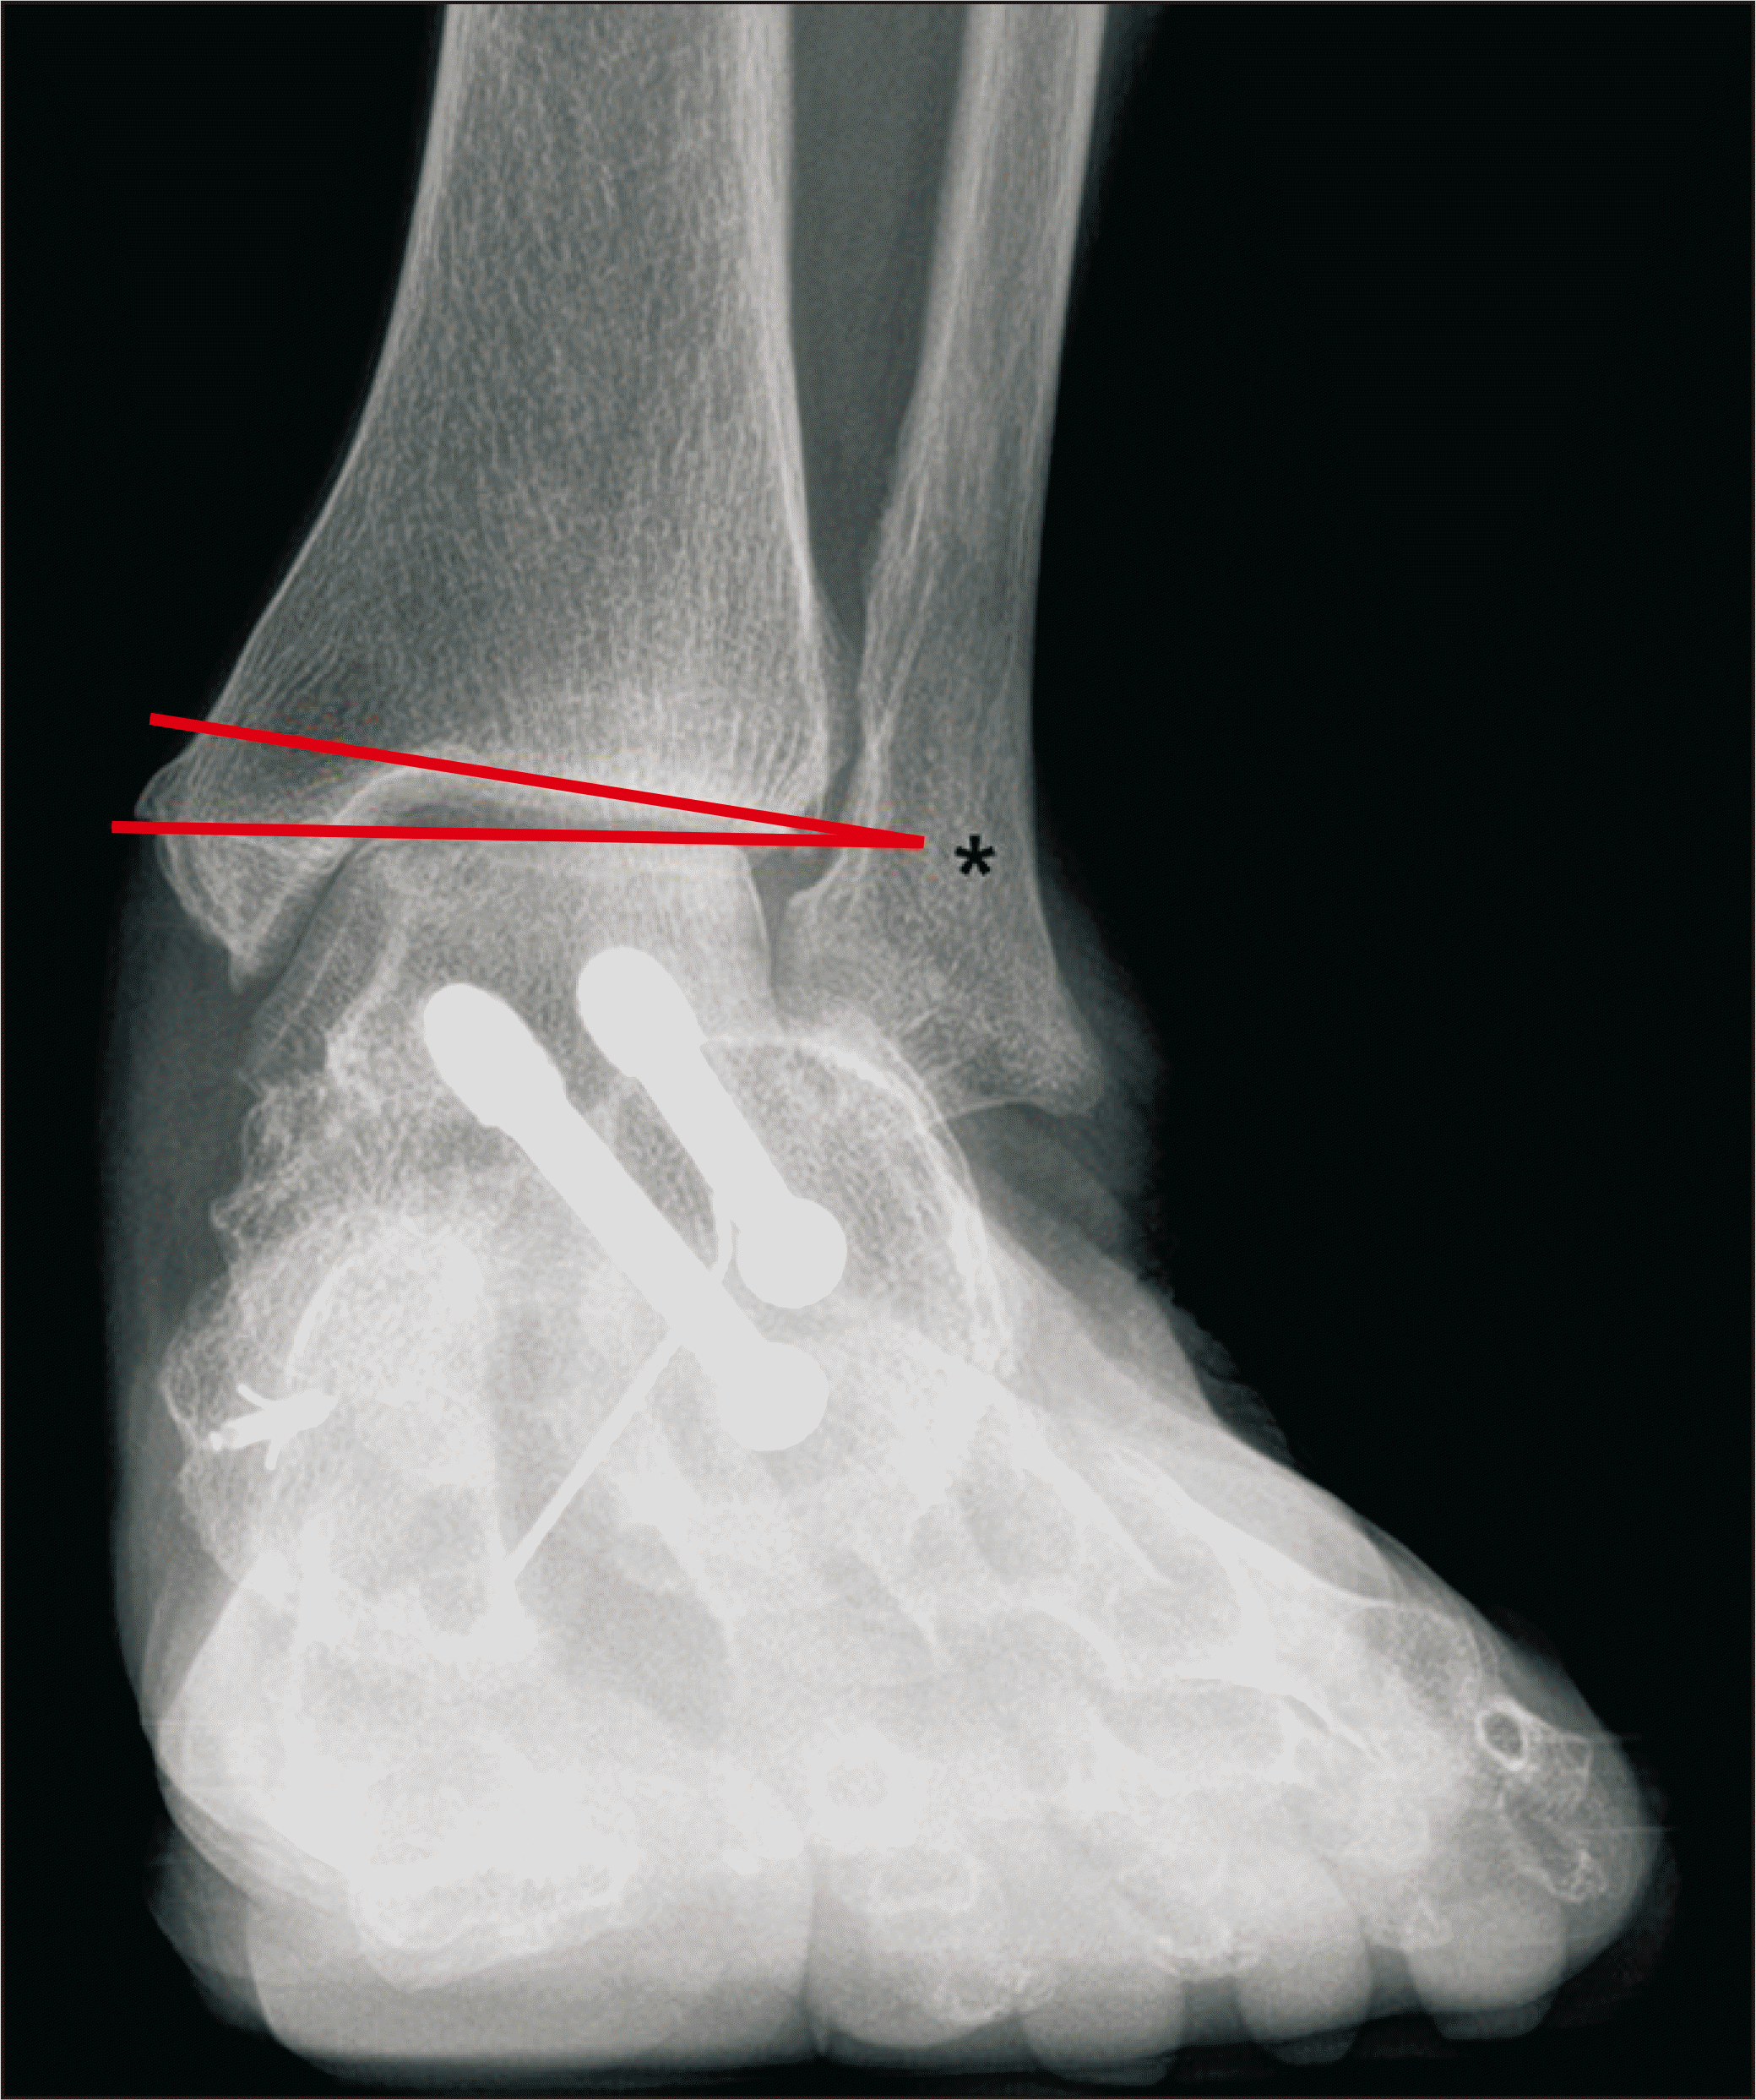

체중부하 방사선 촬영은 편평족의 진단에 있어 가장 표준이 되는 검사로, 체중부하 족부 전후면, 족부 측면, 족관절의 전후면 혹은 모티스 영상(mortise view) 및 후족부 정렬 촬영(hindfoot alignment view)8) 등이 진단을 위해 권고된다.9) 족부 전후면 사진에서는 전족부 혹은 중족부의 외전 정도를 평가할 수 있으며 거주상 관절 피복각(talonavicular coverage angle), 거주상 관절 이탈률(talonavicular uncoverage percent) 등 이를 반영하는 매우 다양한 지표를 측정할 수 있다(Fig. 1). 족부 측면 사진에서는 내측 세로궁의 소실 정도를 평가할 수 있는데, 흔히 쓰이는 지표로는 Meary angle이라 불리는 외측 거골-제 1중족골 각도를 측정할 수 있다(Fig. 2). 또한 족부의 내측주(medial column) 관절들의 족저부 벌어짐(plantar gapping) 정도를 확인하여 내측주 불안정성 정도를 평가할 수 있으며 족근동에서 거골과 종골의 직접적인 충돌 혹은 족근동 주변 골의 경화소견이나 낭종성 병변 등을 통해 족근동 충돌을 간접적으로 확인할 수 있다(Fig. 3). 족관절의 전후방 혹은 모티스 사진에서는 거골의 외반경사(valgus talar tilt)의 유무를 통해 족관절의 불안정성을 평가할 수 있으며 변형이 많이 진행한 경우 비골하 충돌 또한 확인할 수 있다(Fig. 4). 마지막으로, 후족부 정렬 촬영을 통해서는 후족부 외반 변형의 정도를 평가할 수 있는데, 주로 후족부 정렬각(hindfoot alignment angle) 혹은 후족부 모멘트암(hindfoot moment arm)을 측정한다(Fig. 5).10)

새로운 분류체계는 변형의 종류와 위치에 따라 A~E로 나누고, 각 변형의 유연성 유무에 따라 1기 유연성 변형과 2기 강직성 변형으로 분류하였다(Table 2).6) 이러한 변형은 진찰 소견과 체중부하 단순 방사선 촬영을 통해 평가하도록 하였고, 체중부하 전산화 단층촬영의 경우 아직 전세계적으로 사용되고 있지는 않기 때문에 판단기준에서 제외되었다. A형 변형은 후족부 외반 변형으로 후족부가 신체의 정중선으로부터 외측으로 전위된 변형을 뜻한다. 임상적으로 진찰 시 후족부 외반이 관찰되거나, 후족부 정렬 영상에서 후족부 정렬각 혹은 후족부 모멘트암의 증가 등으로 판단할 수 있다(Fig. 5). B형 변형은 전족부 혹은 중족부의 외전 변형으로 전족부나 중족부가 후족부를 기준으로 외측으로 전위된 변형이다. 체중부하 족부 전후면 사진상 거골두에 대한 주상골의 피복(coverage) 정도가 감소하고, 거주상 관절 피복각이 증가한다(Fig. 1). 또한 이 변형에 의해 족근동 충돌이 발생할 수 있으며, 족근동 주변의 압통 및 통증이 발생할 수 있다. 체중부하 족부 측면사진상 족근동에서 거골과 종골의 직접적인 충돌 소견이 보이거나, 족근동 주변의 거골과 종골의 골경화 혹은 골낭종 등을 통해 간접적으로 확인할 수 있다(Fig. 3). C형 변형은 전족부의 내반 변형 혹은 내측주 불안정성으로 임상적으로 후족부를 중립 위치에 고정한 뒤 관찰하였을 때 전족부가 내반을 보이는 변형이다(Fig. 8). 일부에서는 이를 회외 변형으로 불러야 한다는 의견도 있으나 현재 혼용해서 쓰이고 있다.11,20) 내측주 불안정성은 체중부하 족부 측면사진상 거주상 관절, 주상설상 관절(naviculocuneiform joint) 및 족근중족 관절(tarsometatarsal joint)이 배측 불안정증을 보이는 것으로, 영상검사상 족저부 벌어짐 유무 등을 통해 내측주 불안정성의 유무 및 위치를 확인할 수 있다(Fig. 3). D형 변형은 거근관절의 탈구 혹은 아탈구 변형으로 거골이 종골을 기준으로 내회전, 족저굴곡되면서 종골은 거골을 기준으로 외회전, 외반, 외측 전위가 발생하면서 거골하 관절의 아탈구가 발생하고, 심한 경우 비골하 충돌을 일으키게 된다(Fig. 4). E형 변형은 발목관절의 외반 변형이 발생한 경우이며, 족관절의 전후방 혹은 모티스 사진에서 거골의 외반경사로 확인할 수 있다(Fig. 4). 이 분류의 적용은 한 환자에 대해 A 부터 E까지의 변형 유무를 확인하고, 각각의 변형이 유연성 변형인지, 강직성 변형인지에 따라 1기와 2기를 나누는 방식으로 적용한다.

Figure 4

Weight bearing ankle anteroposterior radiograph showing valgus talar tilt and subfibular impingement (*).